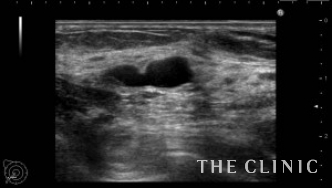

この方は5年前から数回に分けてヒアルロン酸注入を受けられています。通常、ヒアルロン酸は2年程で吸収されていきますが、この方は数回に分けて何度も注入されているため炎症が起こりヒアルロン酸の周囲に被膜を形成してしこりになっていました。エコーにて確認すると、数ミリのものもあります。注入部位も通常であれば乳腺下ですが、この方はバラバラに注入されていて皮下・乳腺内・乳腺下・大胸筋内と様々な層にあり、難易度は最高レベルでした。(右側の画像:ヒアルロン酸が蜂の巣の様に隔壁を作りしこりになっている)